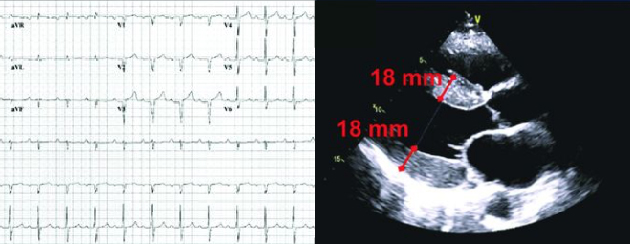

- În ATTR-CM, funcţia diastolică este afectată de depozitele de amiloid din miocard, care determină îngroşarea şi rigidizarea ventriculilor şi implicit debitului cardiac. Abia în stadiile mai avansate de evoluţie a ATTR-CM survine scăderea fracţiei de ejecţie8, 9

- Indiciile imagistice, precum reducerea strainului longitudinal cu sparing pe segmentul apical, pot creşte suspiciunea clinică1, 9